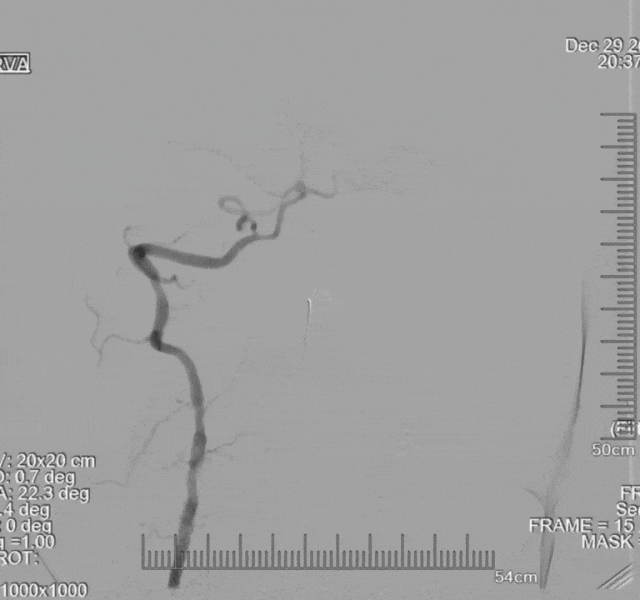

入院前10小时(10:00am),患者于当地县医院行头颅CT未见明显异常,脑电图示右中央、右顶枕、右前中额可见10-14Hz尖波,未予特殊治疗,紧急转至当地市医院。入院前6时(02:30pm),患者于当地市医院行头颈部CTA示:左侧椎动脉V3段纤细,基底动脉起始部以远未显影。

院前CTA示:左椎V3重度狭窄(绿色箭头处),基底动脉起始部以远未显影(红色箭头处)。

院前CTA